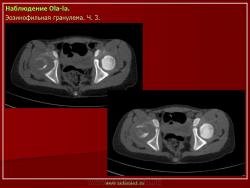

Продолжение.

1.gi_.slayd14.jpg2.gi_.slayd15.jpg3.gi_.slayd16.jpg1.gis_.slayd15.jpg2.gis_.slayd16.jpg3.gis_.slayd17.jpg4.gis_.slayd18.jpg5.gis_.slayd19.jpg6.gis_.slayd20.jpg7.gis_.slayd21.jpg8.gis_.slayd22.jpg9.gis_.slayd23.jpg